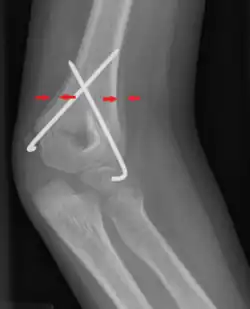

Periosteal reaction on a healing supracondylar fracture

A periosteal reaction is the formation of new bone in response to injury or other stimuli of the periosteum surrounding the bone.[1] It is most often identified on X-ray films of the bones.

A periosteal reaction can result from a large number of causes, including injury and chronic irritation due to a medical condition such as hypertrophic osteopathy, bone healing in response to fracture, chronic stress injuries, subperiosteal hematomas, osteomyelitis, and cancer of the bone. It may also occur as part of thyroid acropachy, a severe sign of the autoimmune thyroid disorder Graves' disease.

The morphological appearance can be helpful in determining the cause of a periosteal reaction (for example, if other features of periostitis are present), but is usually not enough to be definitive. Diagnosis can be helped by establishing if bone formation is localized to a specific point or generalized to a broad area. The appearance of the adjacent bone will give clues as to which of these is the most likely cause.

Appearances include solid, laminated, spiculated, and the Codman triangle.[4]